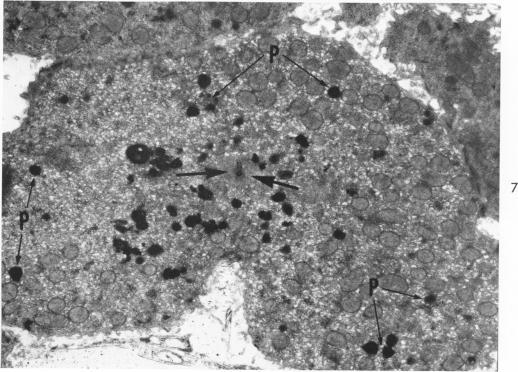

The Movement of Iron-Laden Lysosomes in Rat Liver Cells During Mitosis.

Am J Pathol. 1965 May;46(5):803-27.